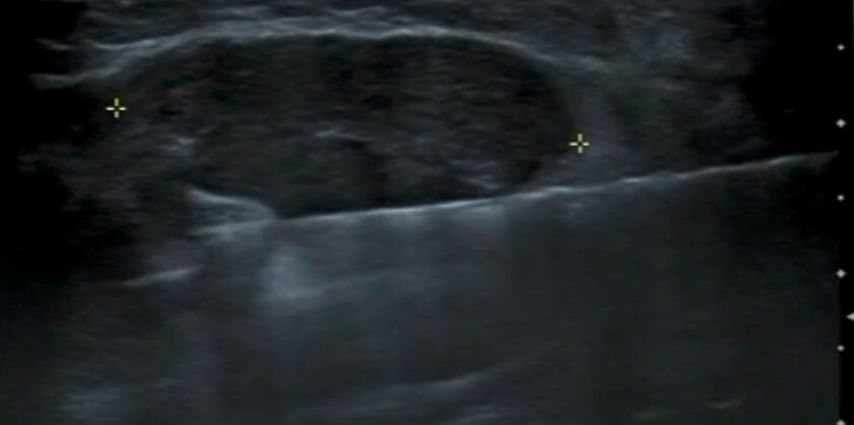

Nach Stichinzision der Haut wird die VAB-Nadel unter ständiger sonografischer Sichtbarkeit dorsal des Zielbefundes positioniert (Abb. 3). Die Richtung der Nadelöffnung entspricht zumeist der Bedienleiste auf dem Handstück des VAB-Gerätes und wird üblicherweise zwischen 45° und 180° Winkelöffnung eingestellt. Die Entfernung der Zielläsion durch schichtweise Schnitte der VAB-Nadel wird unter ständiger US-Kontrolle durchgeführt und die Gewebszylinder werden in einer angeschlossenen Kammer gesammelt. Sollte bei dem Vorgehen eine Blutung einen sonografischen Artefakt verursachen, kann diese durch die Vakuumfunktion der Nadel entfernt werden. Nach der Intervention kann eine Clipeinlage zur Markierung der Biopsiestelle sinnvoll sein. Zur Blutstillung wird eine lokale Kompression durchgeführt und ein Kompressionsverband angelegt. Die Einstichstelle wird durch ein adaptierendes Pflaster versorgt.

Abb. 3: Positionierung der VAB-Nadel dorsal des zu entfernenden Fibroadenoms